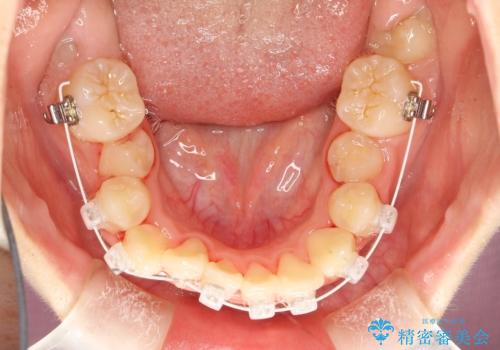

過剰歯と乳歯を抜歯後、リンガルアーチを用いて大まかな移動を行った後、マルチブラケットへ移行し、可及的に正常咬合へと誘導することを試みた。

乳歯・過剰歯を除去し、リンガルアーチを用いて埋伏していた犬歯を牽引、その他おおまかな動きを行った後、マルチブラケットにて永久歯の咬合を誘導しました。